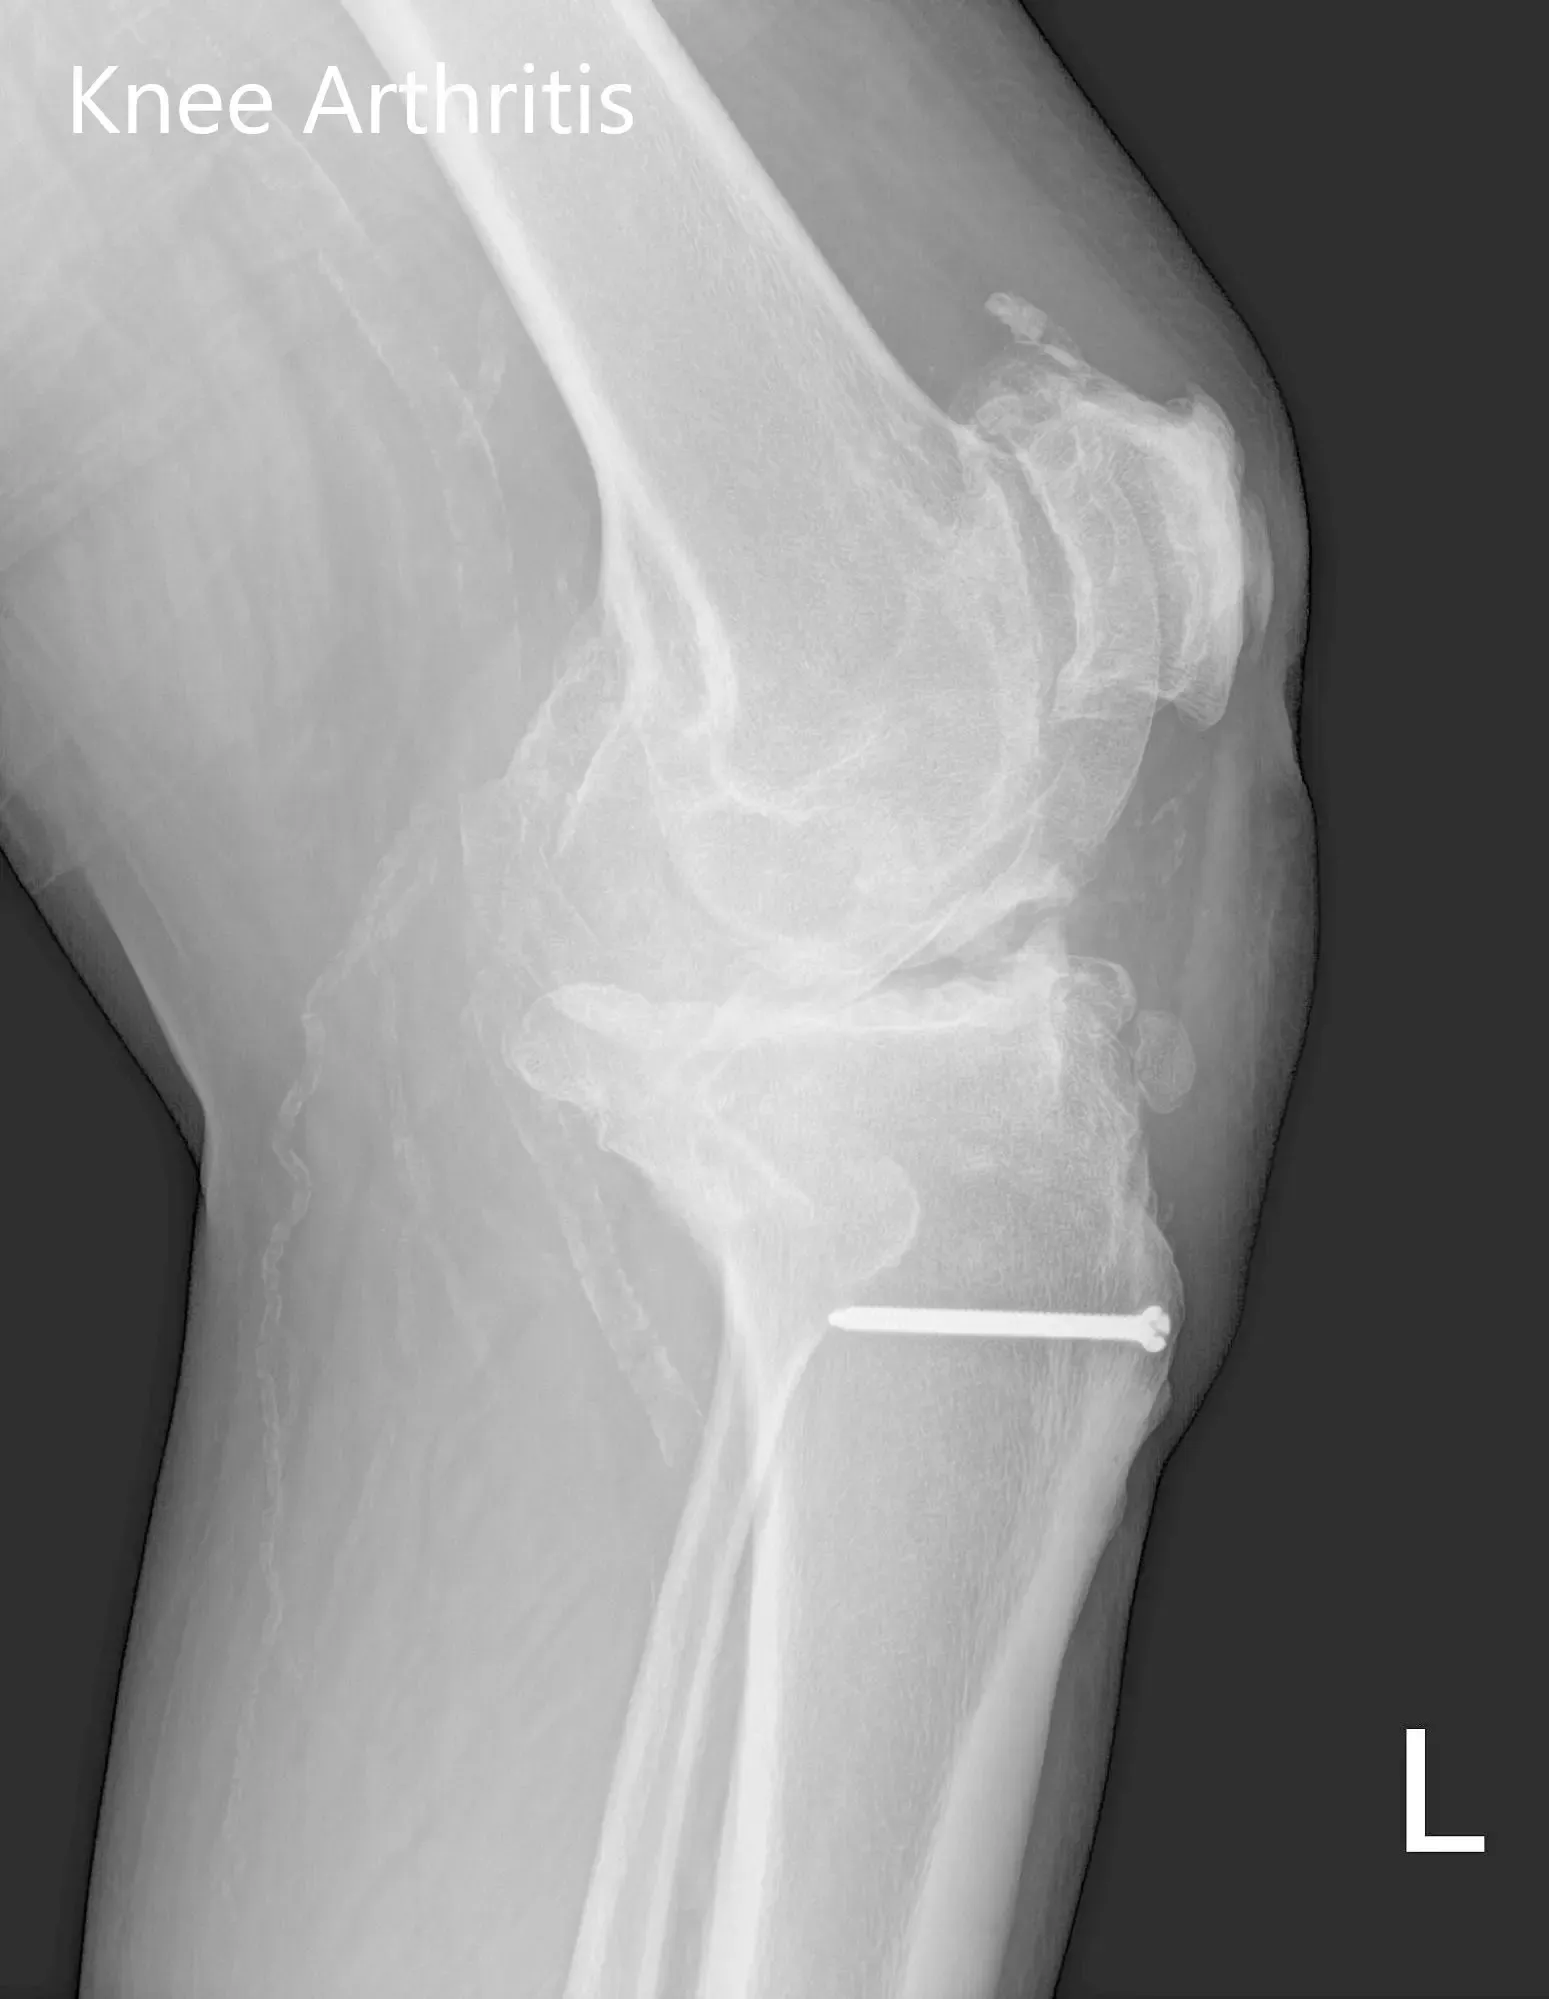

Sus estudios de imagen revelaron osteoartritis tricompartimental de la rodilla izquierda con un perno retenido (perno) en la tibia proximal izquierda. Tras evaluar sus condiciones médicas y examinarse físicamente, se consideró candidata para una prótesis de rodilla personalizada. Se le recomendó someterse solo al lado izquierdo debido a los antecedentes previos de infracciones miocárdicas y luego proceder a la rodilla derecha.

Radiografía preoperatoria de la rodilla izquierda que mostró visión AP y lateral con cambios osteoartríticos degenerativos y hardware retenido en la tibia proximal.